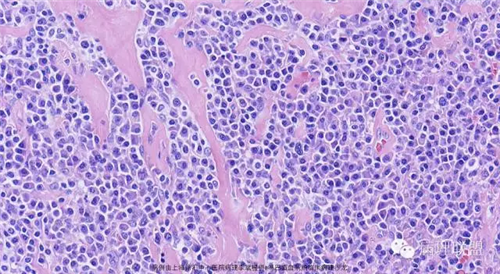

M,79岁,右半结肠粘膜下肿块。大小:6.5*6*6cm球形肿块,切面灰白质硬,界清。第一次取材。